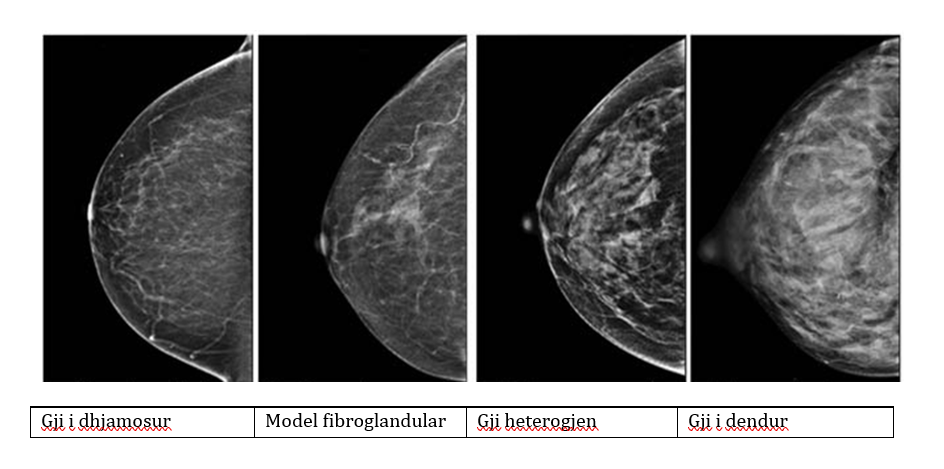

Dendësia e gjirit

Dendësia e gjirit është një term i përdorur në mamografi për të përshkruar se sa ind gjëndrash dhe lidhës ka në gji në raport me indin dhjamor. Nuk mund të ndihet me dorë, por shihet vetëm në mamografi.

Çfarë do të thotë "gjinj të dendur"?

• Gjinjtë janë "të dendur" kur kanë më shumë ind gjëndror dhe lidhës dhe më pak ind dhjamor.

• Në një mamografi, indi i dendur duket i bardhë, si dhe ndryshimet e mundshme të padëshiruara (siç janë tumoret). Kjo e bën më të vështirë shikimin e anomalive tek gratë me gjinj të dendur.